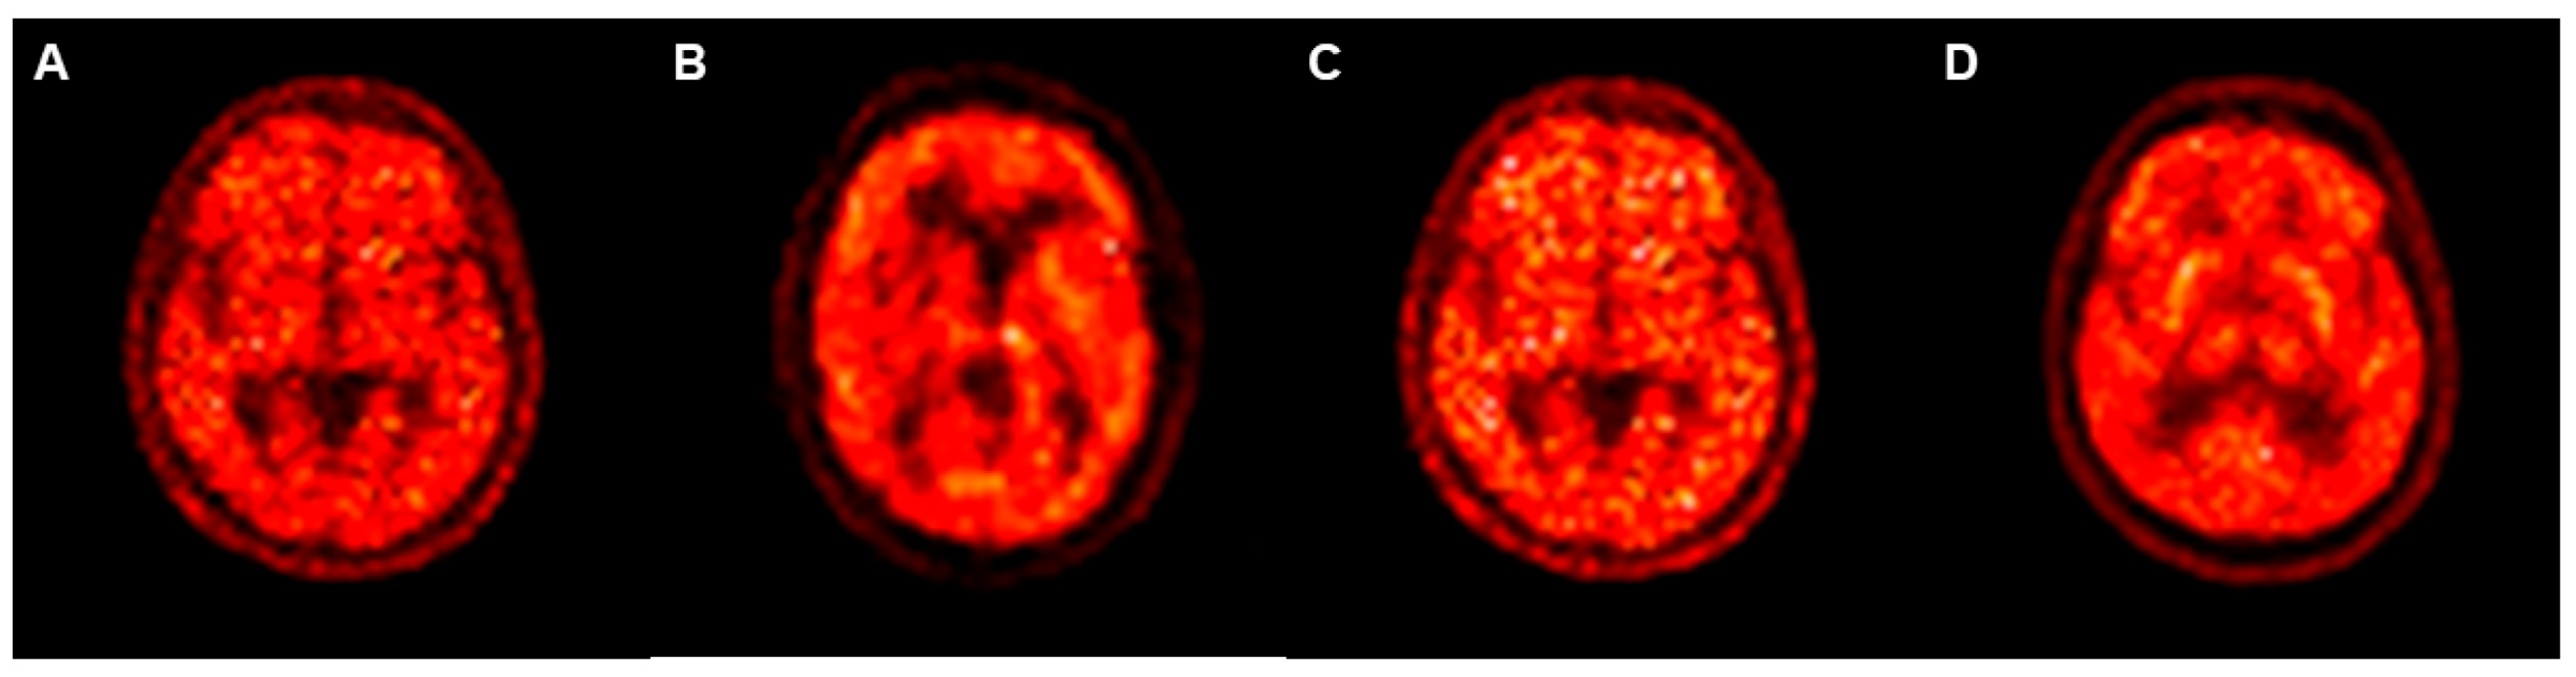

3.2. Differences in SSIM and PSNR Values between PETRE-FDG and PETGE-FDG Images